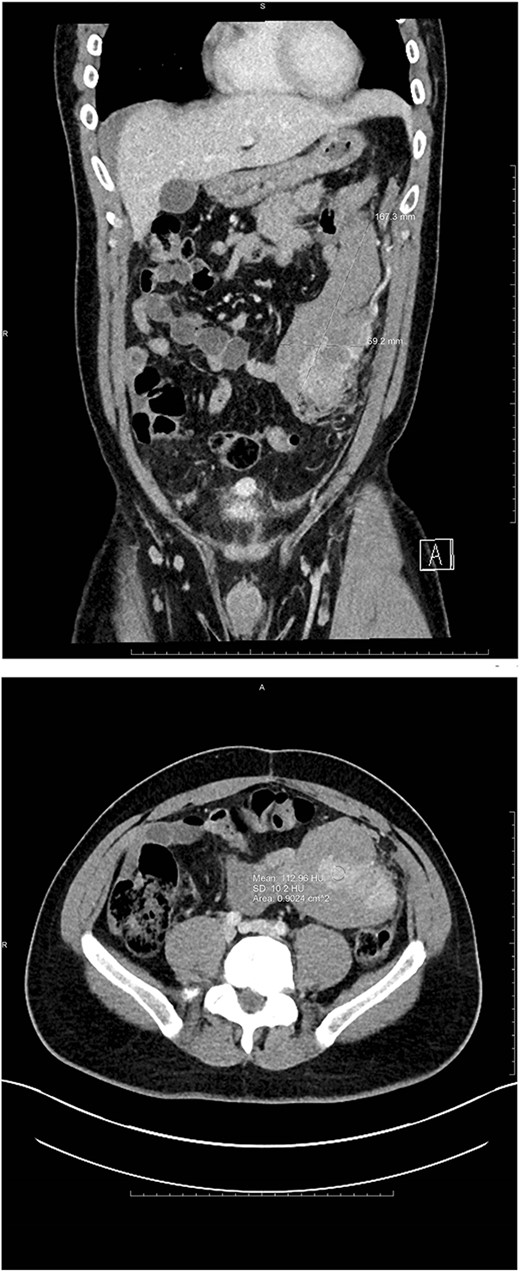

Additional findings included hemorrhagic fluid in the pelvis, right paracolic gutter, and surrounding the right hepatic lobe as well as a small hyper-enhancing mass adjacent to the bladder (see Fig. 2).

Ovoid hyperenhancing lesion anterior to the dome of the bladder, representing an additional area of splenosis.